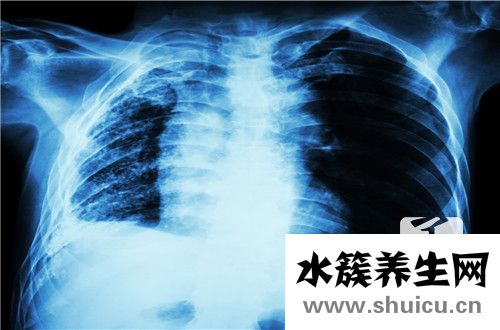

肺癌發生腦轉移,提示肺癌已經處于晚期,治療效果差,患者預后不良。此期患者的1年生存率為15%-35%,而對于那些不適合化療的患者,1年生存率僅為10%。平均來說,晚期非小細胞肺癌患者的5年生存率為2%。

肺癌轉移到腦部常以頭痛、嘔吐、面神經麻痹、偏癱、視物模糊、失語、肌肉無力等為首發癥狀。肺癌腦轉移治愈難度非常大,肺癌腦轉移后能活多久需要根據個人情況來定,一般為1-6個月。腦轉移后的治療主要以腦部放療為主。治療方法有限,效果不佳,可以考慮服用具有抗癌效果的人參皂苷Rh2,它可以幫助緩解病人痛苦,控制病情發展,延長患者生存期。